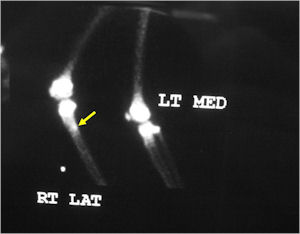

Plain X-Rays:

- Lucent nidus surrounded by a zone of marked sclerosis

- The nidus may demonstrate mineralization/ossification usually from the center outward that appears as a central zone of density within the nidus

- A nidus that is heavily ossified may blend in with the surrounding sclerosis and be difficult to detect on a plain x-ray.

- Periosteal bone is solid, rarely lamellated

- Cortical and subperiosteal osteoid osteomas are usually associated with much more reactive sclerosis than medullary tumors

- The periosteal reaction is continuous and often appears as cortical thickening (benign appearing reaction)

- Intracapsular osteoid osteomas are difficult to identify because there is no periosteum in the intracapsular region and hence a periosteal reaction does not occur.